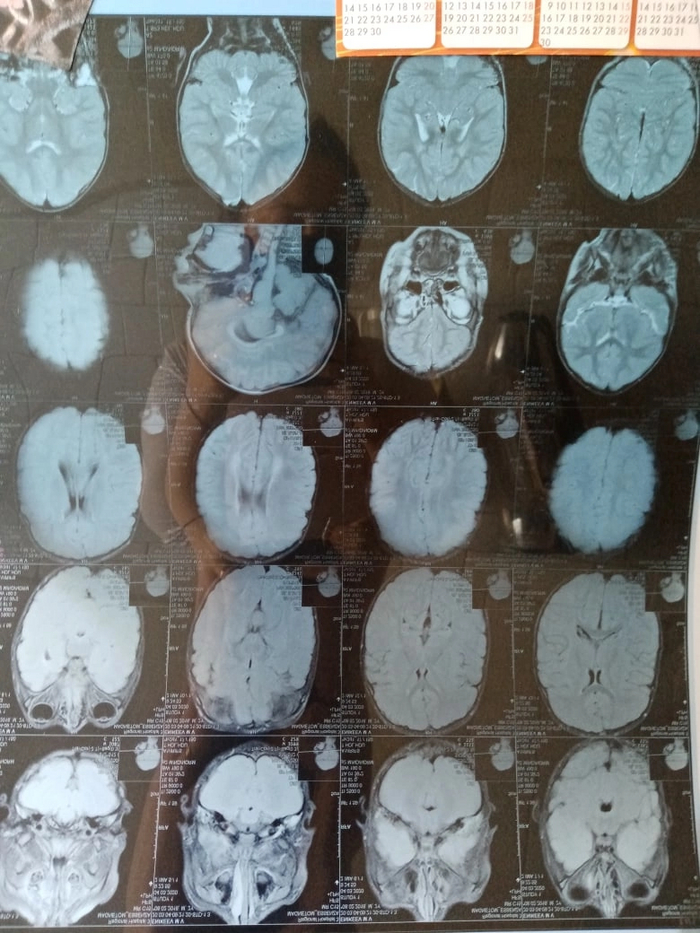

Помогите пожалуйста разобраться что со мной происходит. Может ли вот это все давать такие симптомы как постоянное чувствую давления и распирания в голове и глазах, лопаются сосуды в глазах, ощущение песка, так же отекает лицо, особенно на скулах и эти места краснеют и горят. Волосы стали мертвыми, сухими тонкими и ломкими. Ухудшилось зрение, память, ни на чем не могу концентрировать внимание. Но особенно сильно выматывает вот это давление в голове и глазах . Утром просыпаюсь совершенно разбитая, и с утра эти симптомы особенно сильные. невропатолог глядя на все исследования говорит что это просто нервное, ставит астеноневротическое состояние. Но как же все эти внешние проявления, лопаются сосуды в глазах и на лице, отеки лица, безжизненные волосы.. Ещё часто ощущение что вот вот пойдет кровь носом. А утром когда прочищаю нос то там всегда кровь.

Прикрепила фото в комментариях.